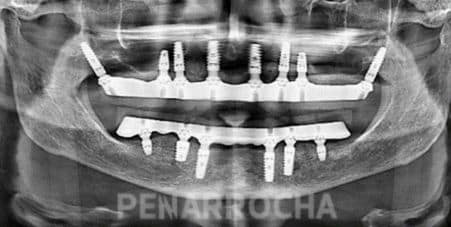

Casos de éxito de implantes dentales con poco hueso en IDIM

En IDIM, contamos con más de 35 años de experiencia tratando casos complejos de implantología dental. A lo largo de nuestra trayectoria hemos logrado recuperar sonrisas de pacientes con condiciones óseas muy complicadas, incluida la falta de hueso suficiente para la colocación de implantes dentales.

Sabemos que la falta de hueso puede ser una preocupación importante, pero gracias a las técnicas avanzadas que utilizamos y a nuestro equipo especializado, hemos logrado devolver a nuestros pacientes no solo una sonrisa estética, sino también una funcionalidad óptima en su boca. Cada paciente es único, y por eso, nos centramos en ofrecer soluciones personalizadas para sus necesidades específicas, teniendo en cuenta la cantidad y calidad del hueso disponible.

Además, entendemos que antes de someterse a un tratamiento tan importante como los implantes dentales, es importante conocer otros casos de pacientes que hayan tenido experiencias satisfactorias. Por eso, a continuación, te compartimos algunos de nuestros casos de éxito más representativos de implantes dentales en pacientes con poco hueso:

Antes:

Después: